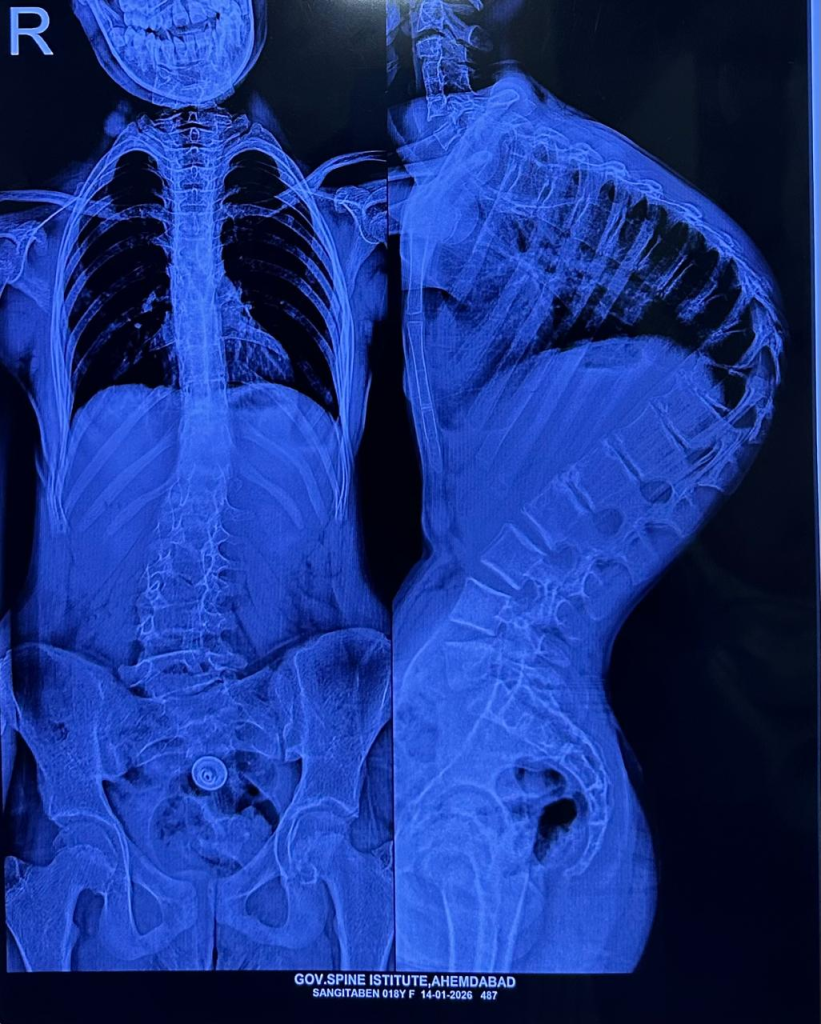

અમદાવાદ સિવિલ મેડિસિટી સ્થિત ગવર્નમેન્ટ સ્પાઈન ઈન્સ્ટિટ્યૂટ ફરી એકવાર મેડિકલ ઇનોવેશન અને માનવીય સેવાના કેન્દ્ર તરીકે ઉભરી આવ્યું છે. ગુજરાત સરકારના આરોગ્ય અને પરિવાર કલ્યાણ વિભાગના સહયોગથી આયોજિત ‘ઈન્ડો-અમેરિકન સ્પાઇન સર્જરી કેમ્પ’ અંતર્ગત કરોડરજ્જુની અત્યંત જટિલ વિકૃતિ ધરાવતા ૭ બાળકોનું સફળ ઓપરેશન કરવામાં આવ્યું હતું. વૈશ્વિક આંકડા મુજબ દર ૧૦૦૦ બાળકોમાં ૧ બાળકમાં જોવા મળતી કાઇફોસિસ અને સ્કોલિયોસિસ જેવી વિકૃતિઓ સામે આ કેમ્પ એક નવી આશા લઈને આવ્યો છે.

‘કાઇફોસ્કોલિયોસિસ’ એક ગંભીર બીમારી છે, જેમાં બાળકની કરોડરજ્જુ સાપની જેમ વાંકી વળી જાય છે, તેની સારવાર સામાન્ય મધ્યમ વર્ગ માટે એક સ્વપ્ન સમાન હોય છે. પરંતુ, ઈન્ડો-અમેરિકન સર્જરી કેમ્પના માધ્યમથી આ સ્વપ્ન હકીકત બન્યું છે.

સર્જરીની જટિલતા અંગે ઈન્ડો-અમેરિકન સર્જરી કેમ્પના ડૉક્ટરો જણાવે છે કે, આ એક અત્યંત જટિલ સર્જરી છે. સરેરાશ ૪ થી ૫ કલાક સુધી ચાલતી આ સર્જરીમાં કરોડરજ્જુને સીધી કરતી વખતે અત્યંત નાજુક ચેતાઓ (Nerves) અને રક્તવાહિનીઓ વચ્ચે કામ કરવાનું હોય છે.

સર્જરી દરમિયાન મુખ્ય પડકાર સતત ‘ન્યુરો-મોનિટરિંગ’નો હોય છે. જો કોઈ પણ પગલું ખોટું પડે, તો મુખ્ય રક્તવાહિનીની ઈજાને કારણે દર્દીનો જીવ જઈ શકે છે અથવા જીવનભરનો લકવો (Paralysis) આવી શકે છે. આ જોખમને ખાળવા માટે અમેરિકન ન્યુરો-મોનિટરિંગ ટીમ અને એનેસ્થેસિયા નિષ્ણાતોએ પણ ટેકનિકલ સહયોગ આપ્યો હતો.

આર્થિક પાસા પર નજર કરીએ તો, આ પ્રકારની જટિલ સર્જરીનો ખર્ચ ખાનગી હોસ્પિટલોમાં રૂ. ૫ થી ૧૦ લાખ જેટલો આંકવામાં આવે છે. ગવર્નમેન્ટ સ્પાઈન ઈન્સ્ટિટ્યૂટ વર્ષ દરમિયાન આવી ૩૦ થી ૪૦ સર્જરીઓ કરે છે. આ કેમ્પમાં ૯ વર્ષના એક બાળક પર ‘ગ્રોઇંગ રોડ સર્જરી’ કરવામાં આવી હતી, જે આધુનિક મેડિકલ સાયન્સનું શ્રેષ્ઠ ઉદાહરણ છે. આ ‘ગ્રોઇંગ રોડ સર્જરી’ બાળકની ઉંમર વધવાની સાથે તેની કરોડરજ્જુને સીધી રાખવામાં મદદ કરશે.